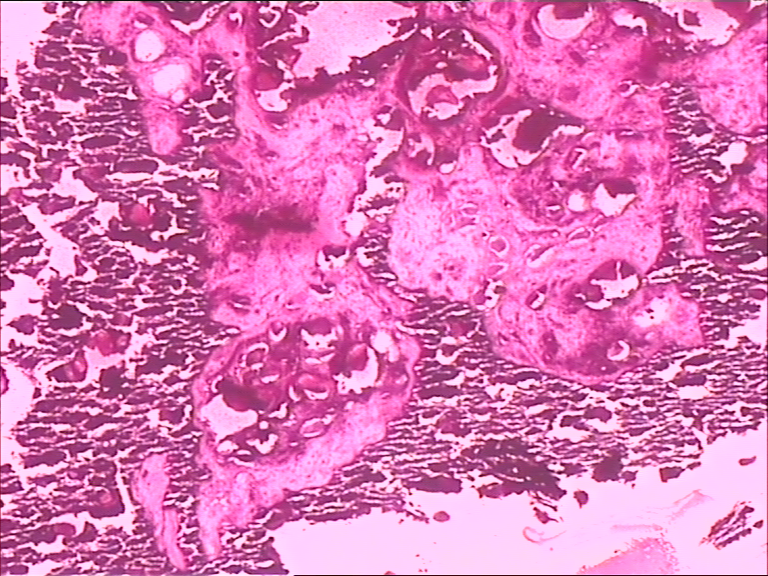

腰部皮下肿块

性别

女

年龄

44岁

临床诊断

腰部皮下肿块待查

一般病史

发现腰部肿块一年,渐增大,无压痛,无红肿。

标本名称

腰部正中偏右皮下肿块

大体所见

肿块大小3*2.5*1.5cm,未见明显包膜,切面灰白、灰黄,可见部分钙化。

图1

是否考虑钙化性腱膜纤维瘤

瘤样钙盐沉着